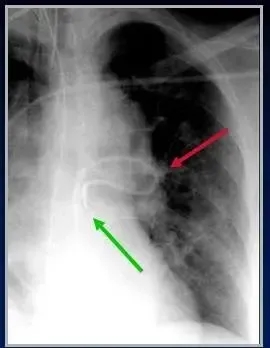

图:肺动脉漂浮导管在左肺动脉内折返(红箭),末端进入右心室(绿箭)。